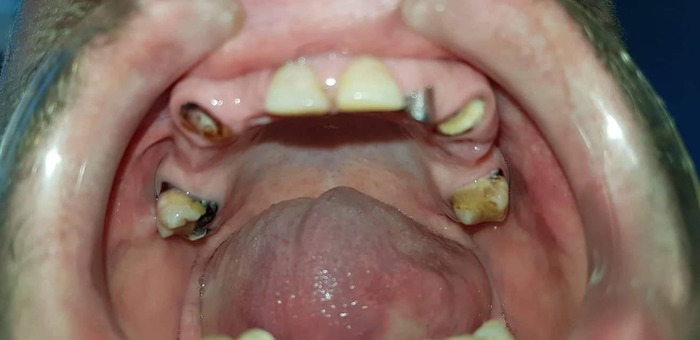

Теперь - как это все дело выглядело в реале:

Вот честно, пока я не увидел именно эти две фотки - я слабо осознавал, какой именно у меня пипец во рту. Каждое утро в зеркале это воспринималось немного не так. Передергивало, конечно, но было привычно. Кстати, все эти фото я увидел уже сильно после лечения и никакого влияния на мое решение лечиться у Георгия они не оказали - не успели )))

А дальше, 3 ноября, за 3 часа времени со мной сделали вот это:

Вот снимки через 5 часов после операции: